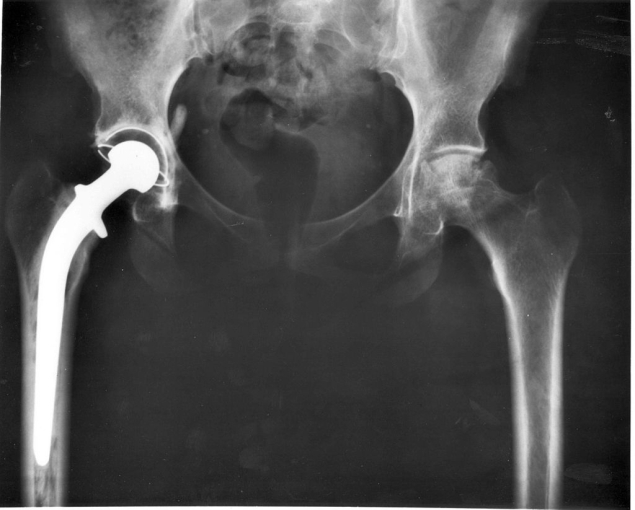

Implanty medyczne, takie jak endoprotezy czy implanty stomatologiczne, wykonywane są na ogół z metali (np. stopów tytanu). Nie są to jednak elementy lite, nie mogłyby bowiem wówczas zintegrować się z tkanką. Dopiero kiedy nada się im odpowiednią porowatość, tkanka (na przykład kość) może je swobodnie przerastać. Dzięki temu implant pozostaje na swym miejscu i dobrze spełnia swoją funkcję.

Niestety, maleńkie pory w strukturze implantu stwarzają przyjazne środowisko nie tylko dla tkanki, ale i dla bakterii. W takim przypadku groźne mikroorganizmy nie tylko osadzają się na powierzchni, ale i ochoczo penetrują wnętrze implantu – a ryzyko infekcji gwałtownie wzrasta.

Oczywiście implanty nie są zostawiane bez odpowiedniej ochrony – aby zapobiec rozwojowi bakterii, a równocześnie poprawić integrację z tkanką, stosuje się odpowiednie powłoki. Te jednak, które wykorzystuje się obecnie, są oparte głównie na hydroksyapatycie (naturalnie występującym w kościach związku mineralnym) lub bioaktywnym szkle i w trakcie obróbki cieplnej bardzo łatwo pękają. A każda szczelina to zaproszenie dla bakterii.